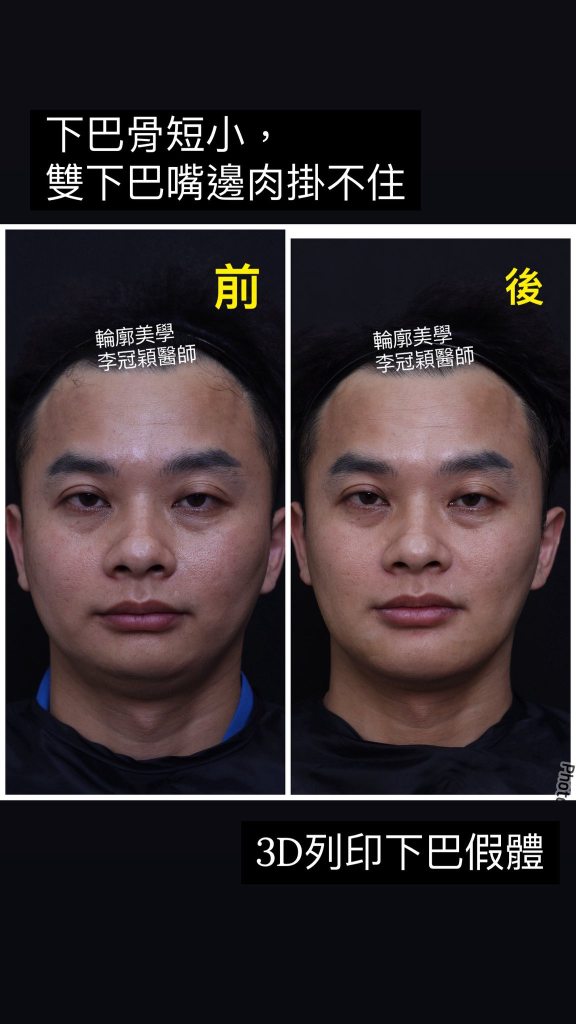

下圖:後縮小下巴會堆積雙下巴和嘴邊肉皮膚,視覺老態。經過客製化3D導航下巴改善外觀老態,提升年輕化。

過短後縮下巴,因組織支撐力弱而容易有雙下巴(上圖),嘴邊肉(下圖)以及下顎腺不明顯,整體而言除了失衡還有點流失下垂的『老態』。